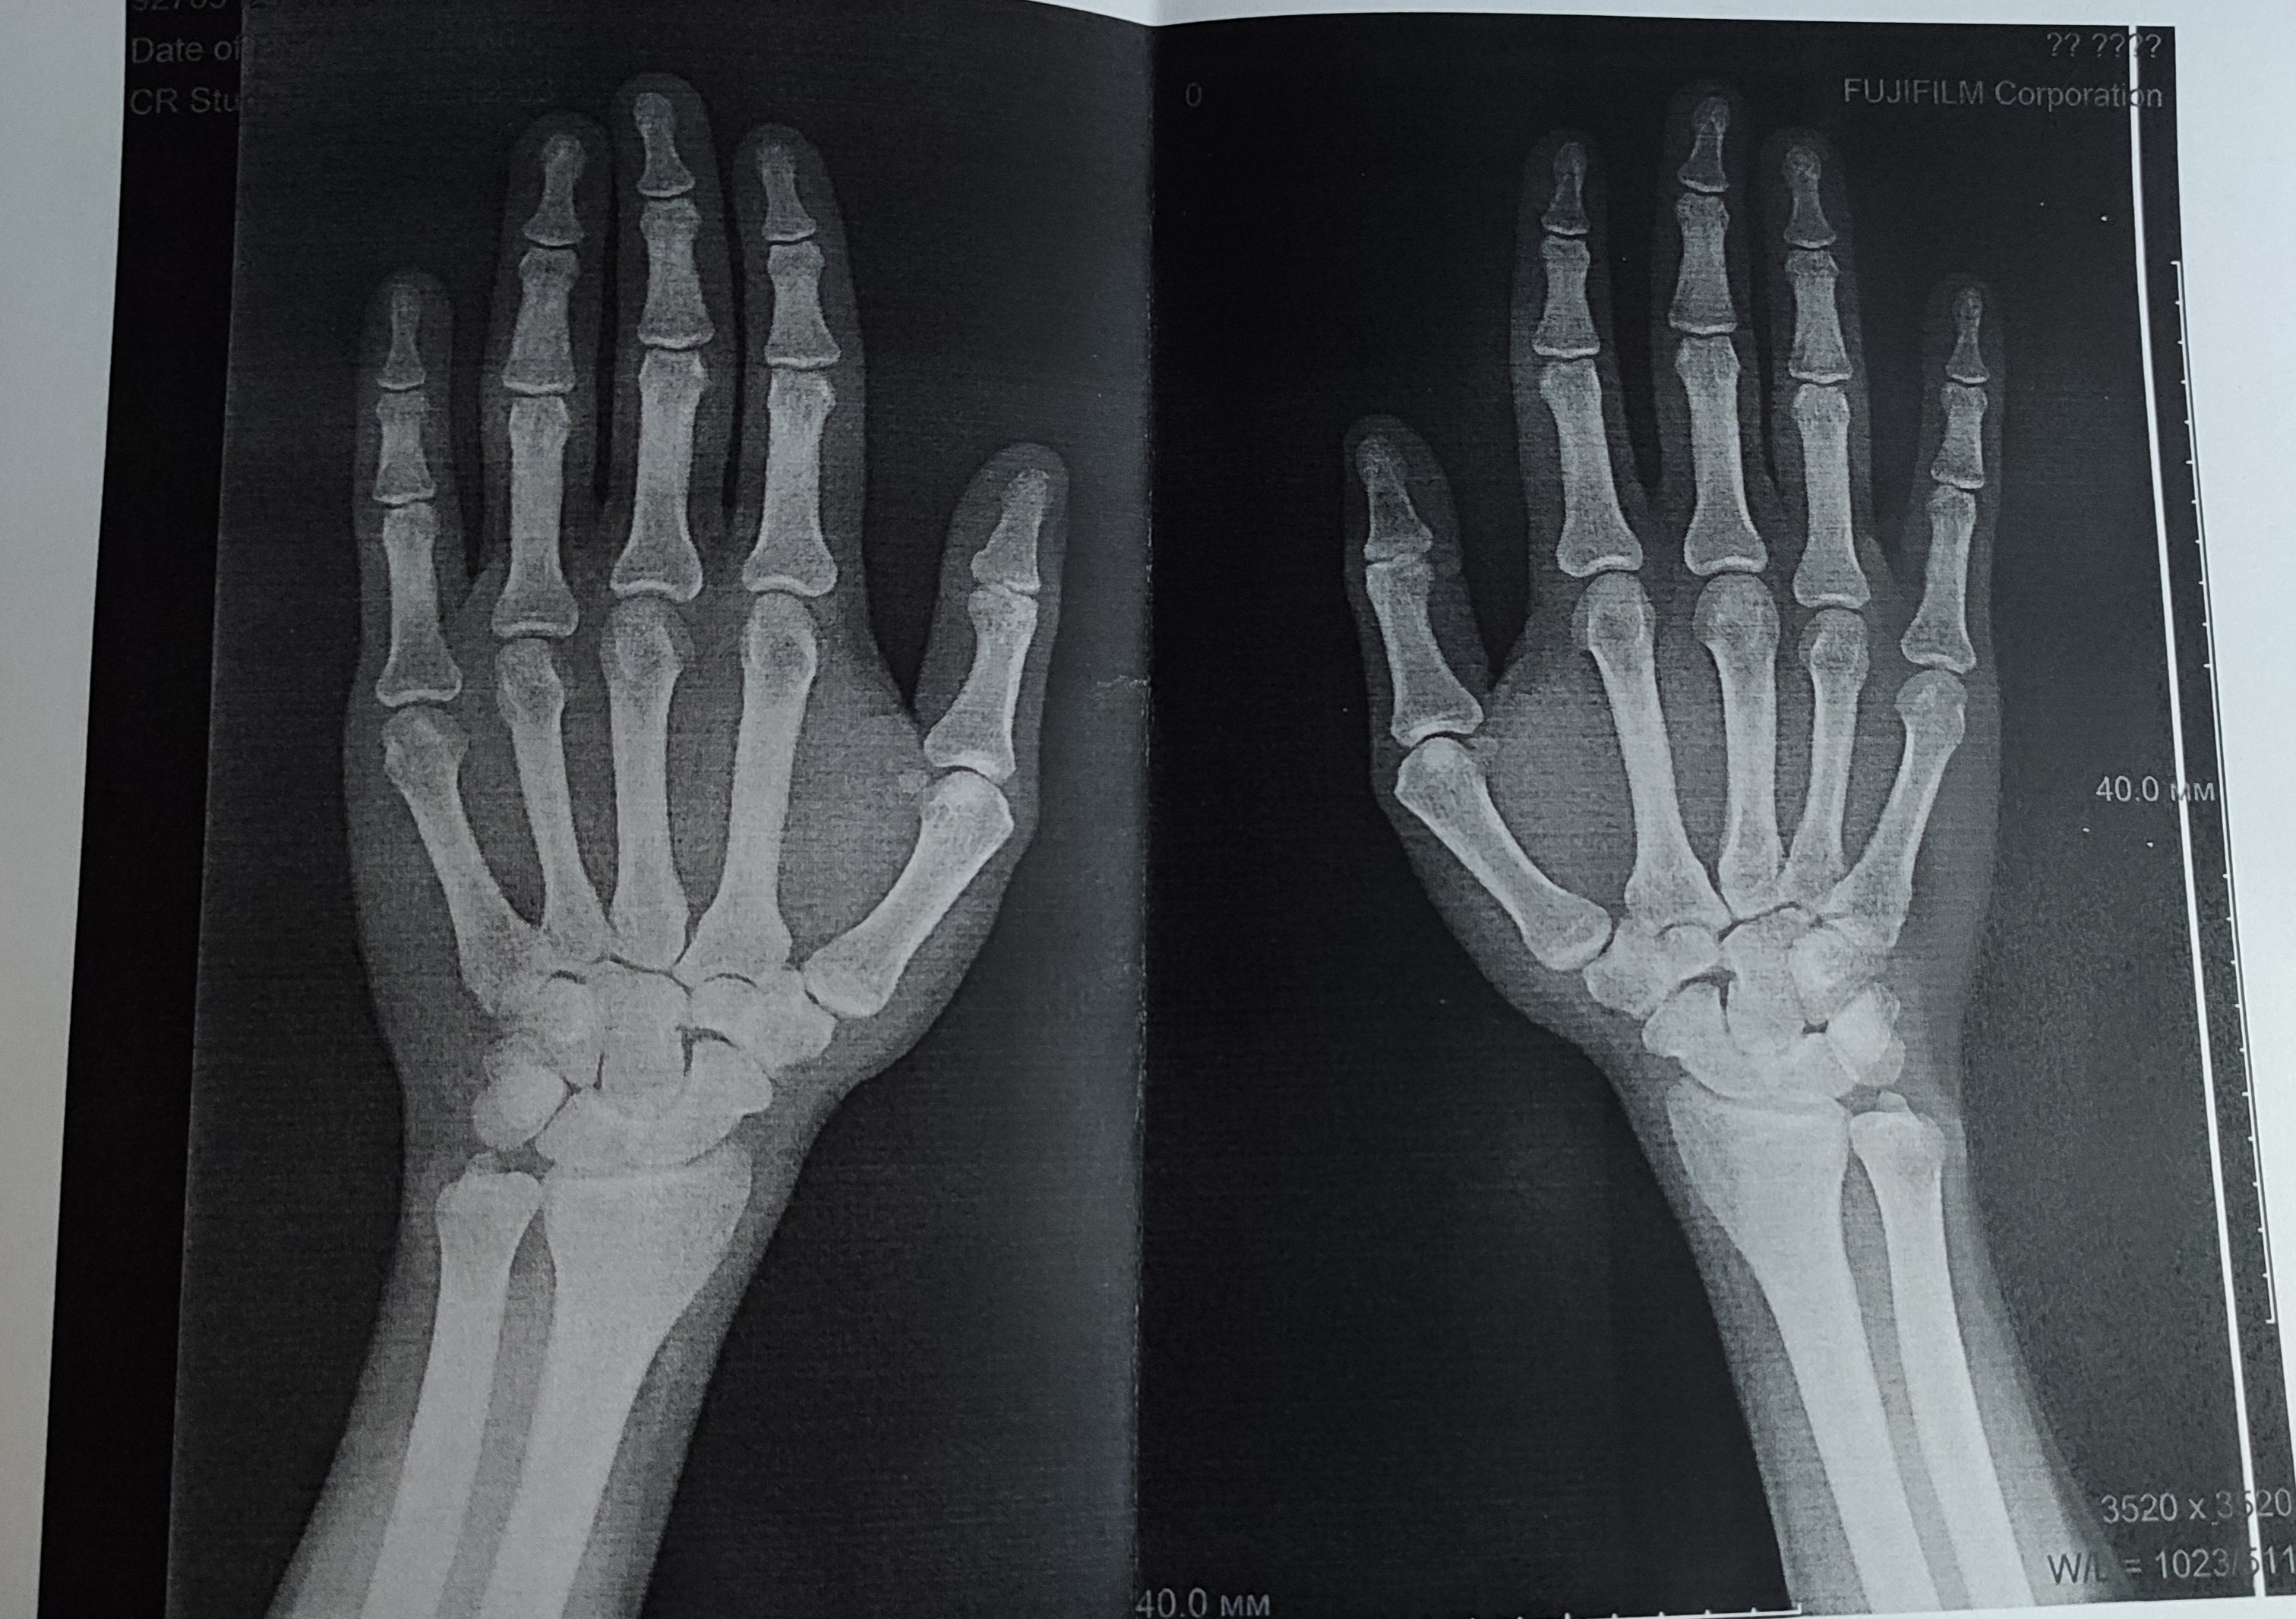

Подборка рентгеновских снимков лучезапястного сустава

Раздел: Объективный взгляд